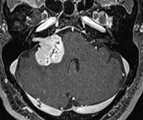

以下の画像に呈示するような脳幹や小脳を圧迫する大きい腫瘍に対しては、開頭手術が優先されます。手術中に神経刺激装置・聴性脳幹反応など電気生理学的モニタリングを併用し、1つ1つの手術操作によって神経機能を損傷していないか随時チェックしながら手術を行っており、術後後遺症の予防に努めています。